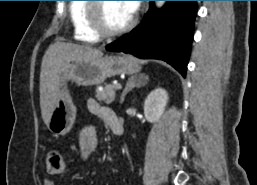

Одним из наиболее информативных методов диагностики заболеваний надпочечников является мультиспиральная компьютерная томография. МСКТ надпочечников относится к лучевым методам исследования, то есть для получения послойного изображения структуры органа используется проникающая способность рентгеновских лучей.

Кроме нативной компьютерной томографии МСКТ надпочечников проводится с применением рентгеноконтрастного вещества на основе йода. Контраст вводится пациенту внутривенно и усиливает визуализацию новообразований на фоне неизмененных тканей. Контрастирование позволяет, в первую очередь, обнаружить опухоли минимальных размеров и определить характер васкуляризации, что особенно важно при онкологических процессах для назначения своевременного лечения.

В клинике «Доступная медицина» мультиспиральная КТ надпочечников выполняется на современных компьютерных томографах экспертного класса TOSHIBA AQUILION, которые производят множество послойных снимков за несколько секунд. Быстрота исследования обеспечивает пониженный уровень лучевой нагрузки на пациента, а благодаря инновационным компьютерным программам томограф создает трехмерные модели органа, позволяющие оценить структуру надпочечников и окружающие ткани.